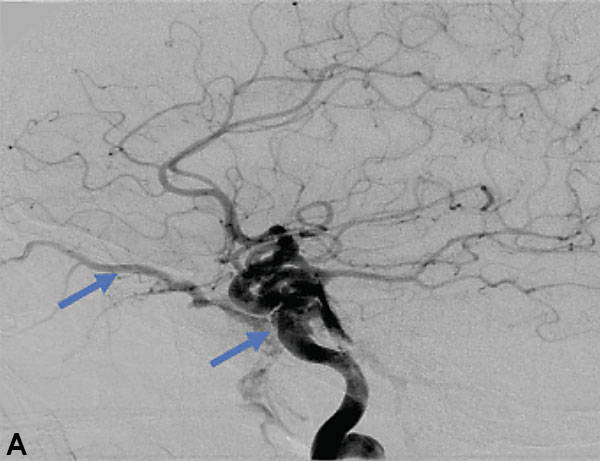

Collateral venous drainage into the orbit and skull base was observed (Figure A). After successful cannulation of the direct aperture between the right carotid artery and the cavernous sinus, balloon-assisted coil embolization of the posterolateral compartment was performed until the fistula was closed (Figure B and C). He experienced immediate cessation of his pulsatile tinnitus with an early improvement of the right VI nerve palsy and near-complete recovery of his vision within 6 weeks

Figure: (A) Right ICA Cavernous Fistula with Venous Shunting (B) Balloon Assisted Coil Embolization (C) Fistula Cured Post Embolization

A 59-year-old man who is otherwise healthy presented to his PCP with progressive right-sided pulsatile tinnitus for 4-6 weeks. His PCP and ENT evaluated him extensively and prescribed multiple courses of steroids and subsequent unremarkable MRI and MRA imaging. He developed acute onset diplopia secondary to a new partial right VI nerve palsy several days prior to our evaluation. A cerebral angiogram confirmed the presence of a high flow direct fistula of the right internal carotid artery–right cavernous sinus.